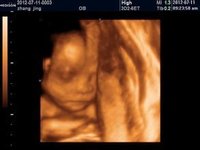

1、重度腦室增寬:(腦室寬度≥15 mm,也可稱為腦積水)指的是腦脊液過多積聚於腦室系統中,側腦室系統擴張,壓力升高,超聲檢查時表現為腦室增寬。一般側腦室三角區增寬達1.5厘米認為腦室擴大,且越寬程度越重。如果三角區寬1.2~1.4厘米,脈絡叢占滿腦室內大於50%時,一般認為正常。如脈絡叢縮小並呈懸掛狀態時,則認為有腦積水存在。

2、輕度側腦室增寬:定義為側腦室直徑≥10mm, 而≤15mm。而側腦室直徑<10mm被認為屬正常生理範圍。

側腦室增寬3、孤立性輕度側腦室增寬:是指產前系統超聲檢查無其他異常發現的病例。約10%的孤立性輕度側腦室增寬的胎兒為染色體異常,其中最多見的為21三體,孕期病毒感染特別是巨細胞病毒感染晚孕時也常會導致孤立性側腦室增寬及腦室旁混合回聲等異常表現。